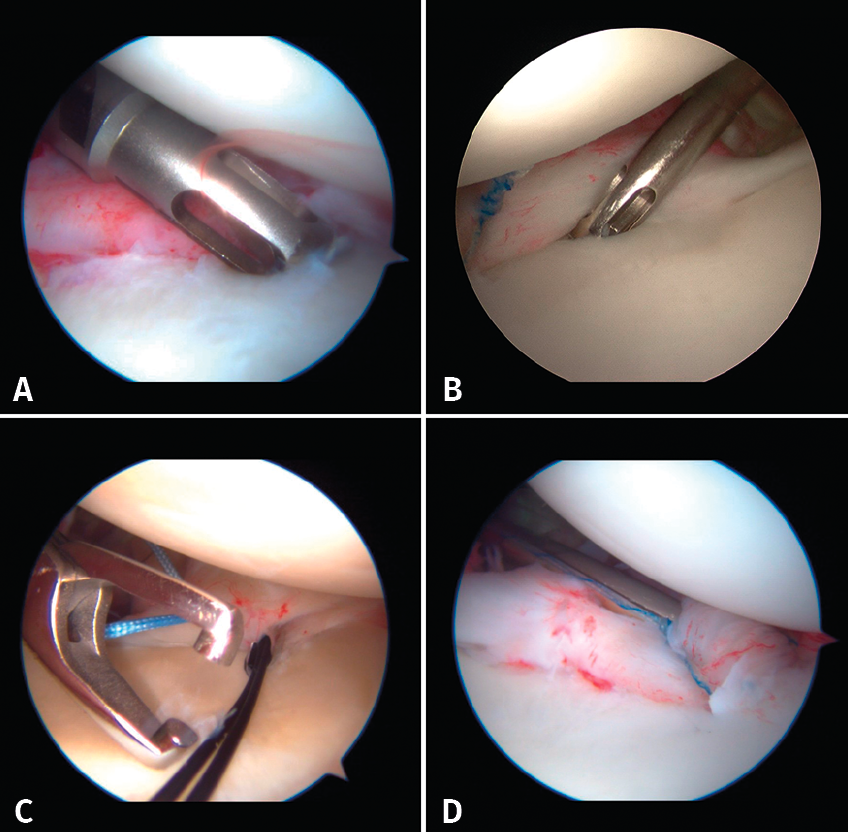

The implants are to be placed at 45º from the joint surface adjacent to the margin of the anterior cartilage, taking care not to medialize them over the neck of the glenoid cavity (Figures 8A and B). We start with the lowest implant; depending on the extent of the lesion, we will need 3, 4 or 5 implants spaced 3-5 mm apart.

Capsulolabral repair can be carried out in different ways, since a number of suture passer systems are available: indirect nitinol devices (these require two steps, but are less damaging to the tissues) or direct passer forceps (involving a single step, but causing more damage).

If a direct system is used, we pass direct penetrating-suture retrieval forceps from anterior to posterior, tunnelling the tissue to be sutured and taking one of the implant threads for knotting to the post. This in all cases will be the thread passing through the tissue, and we try to keep the knot of the thread anterior to the reconstructed tissue without friction against the humeral joint surface. This same step can be made with indirect passer forceps, tunnelling a nitinol wire through the tissue (Figure 8C), allowing us to grasp and then knot one of the implant threads (Figure 8D).

Figure 8. A: placement of implants; B: placement of implants; C: passing of indirect forceps preloaded with a nitinol wire; D: knotting of the thread.